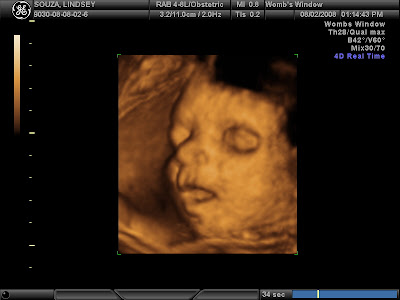

open eyes again

This was after he rolled over. Look at his thumb on his temple and his sweet little ear